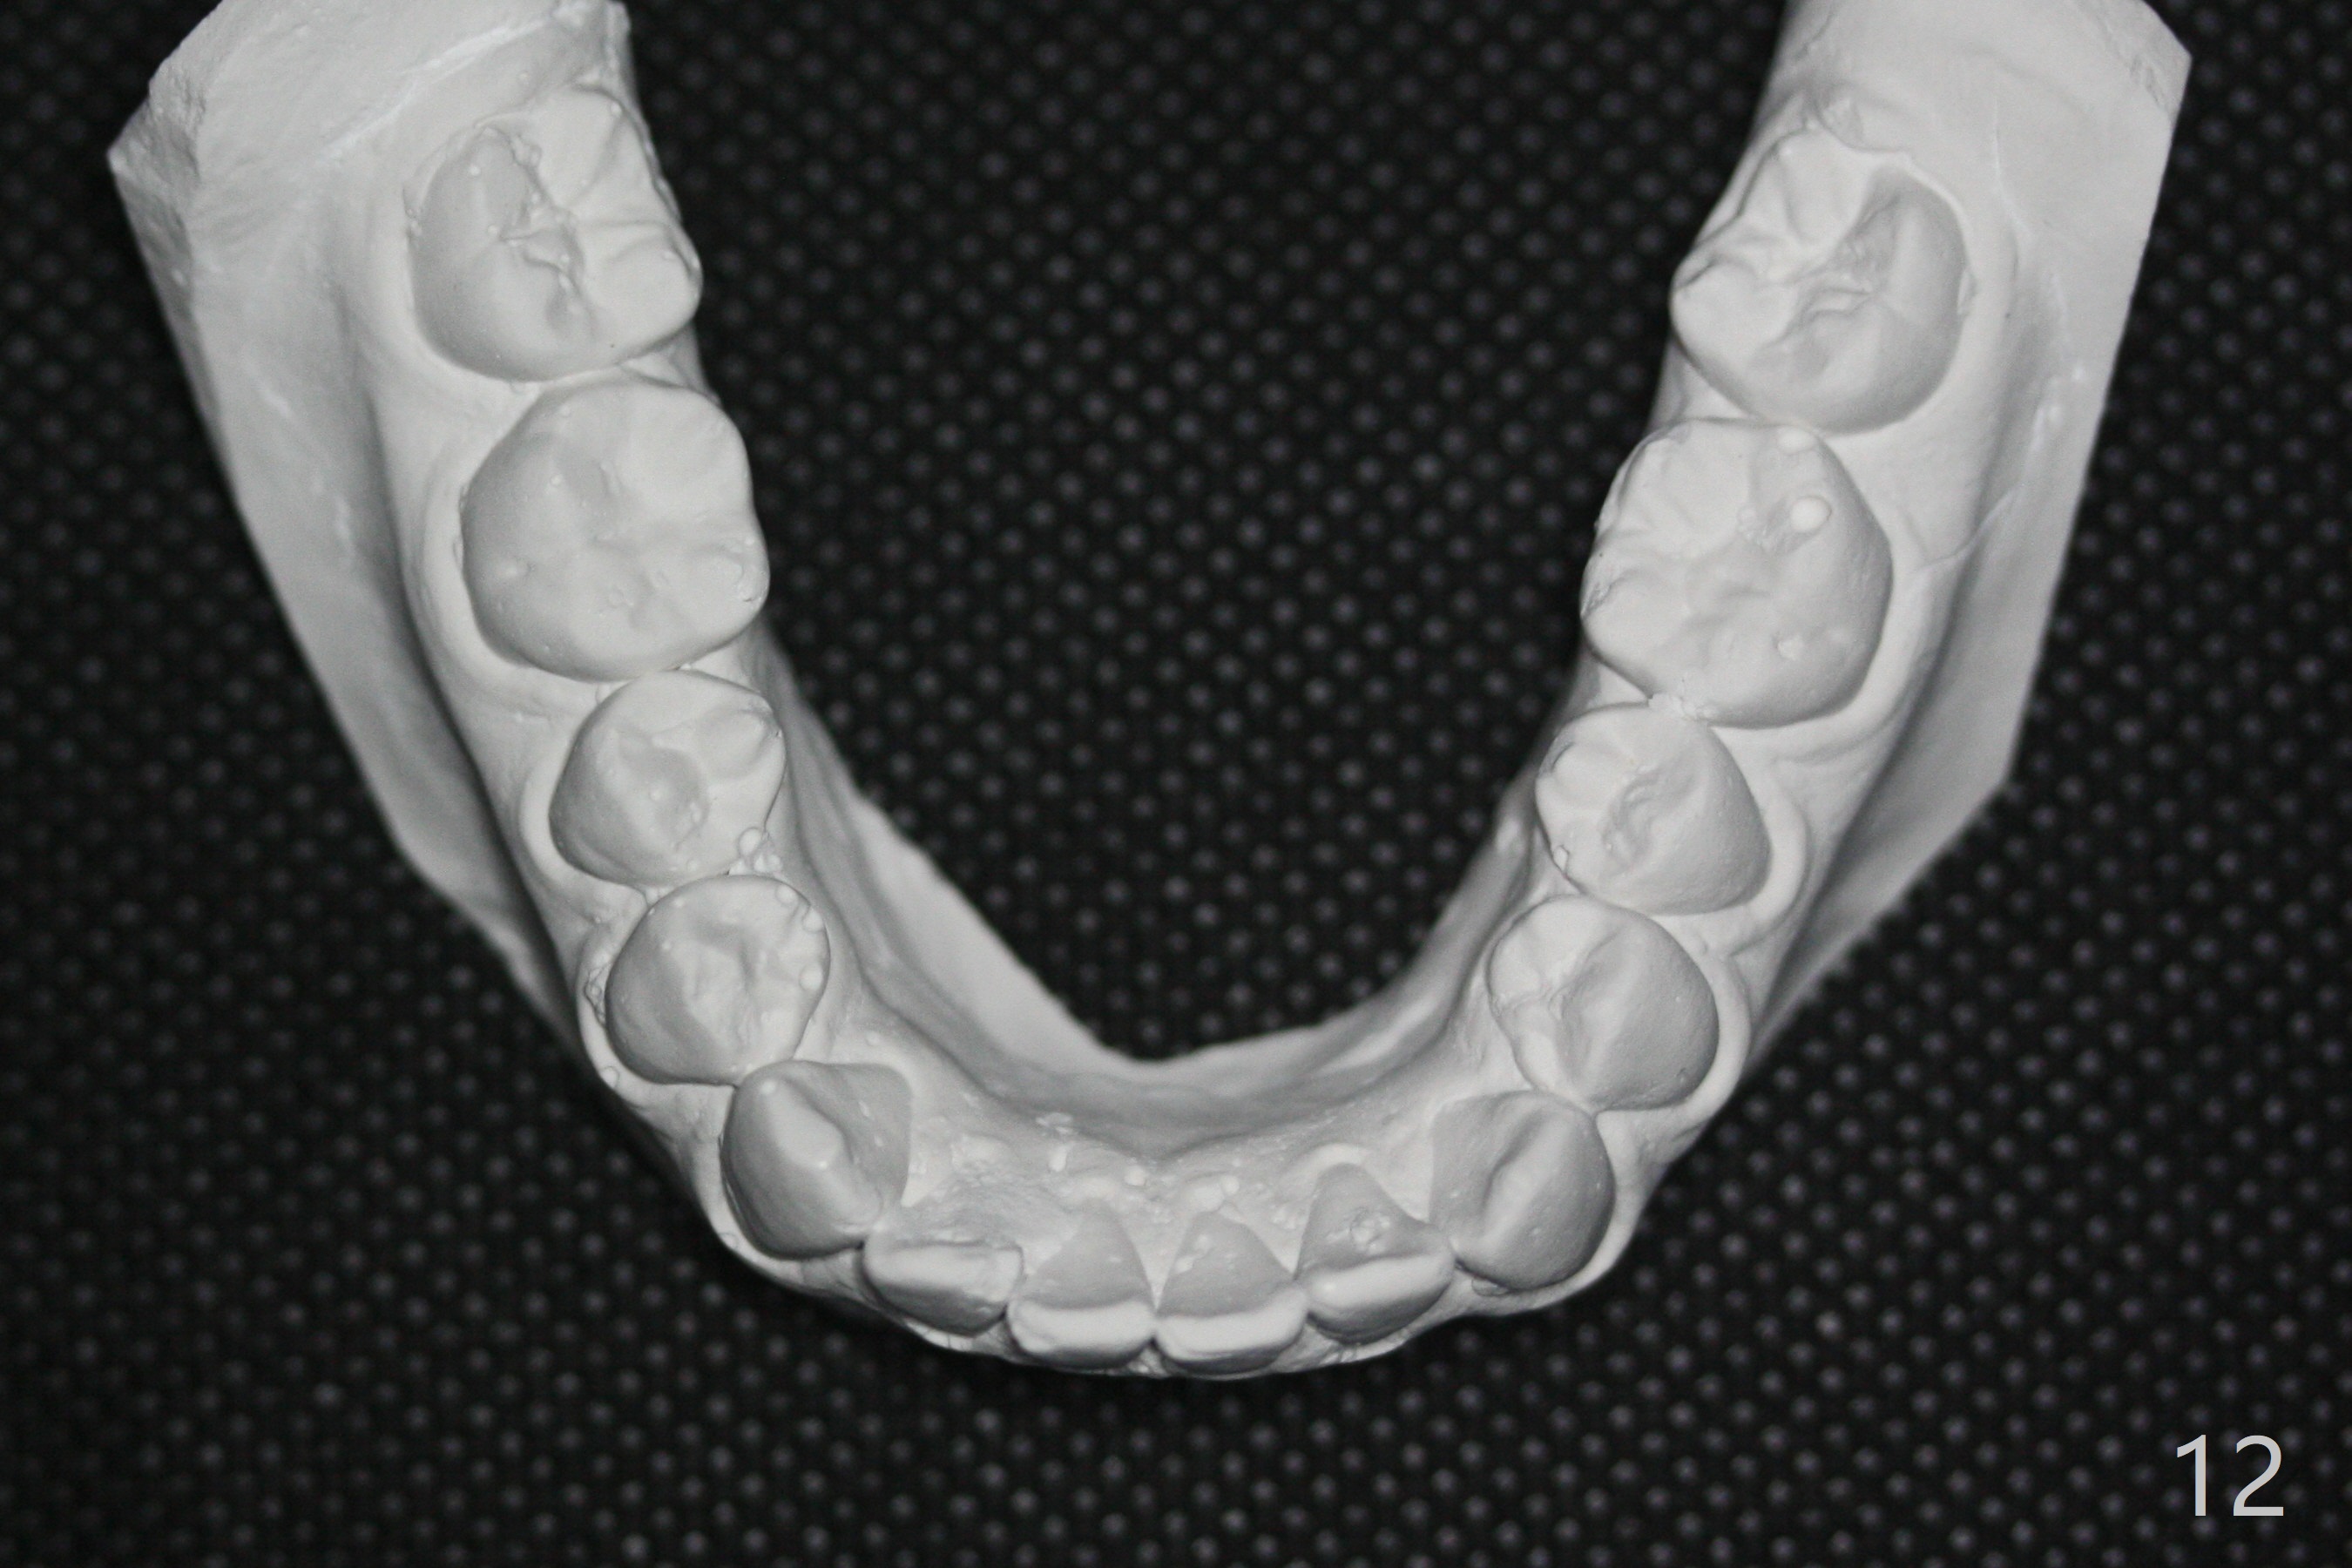

| Pre-op (11 y/o) | Post-op (12 y/o) | Follow Up (14 y/o) |

A 11-year-old man starts orthodontic treatment and finishes in 9 months. Two years later crowding relapses because of loss of suck down retainers. It appears that lingual retainer is necessary.